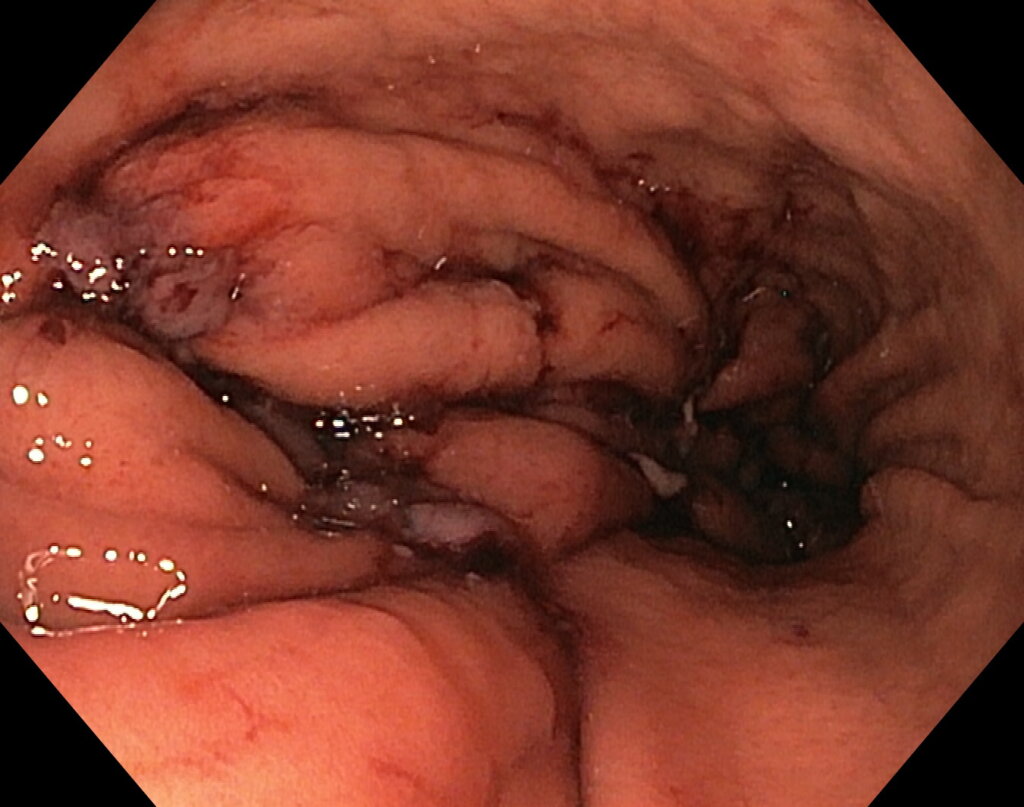

Под видеоконтролем выполнена эндоскопическая рукавная гастропластика: сшивание стенок желудка при помощи аппарата Overstitch Boston Scientific по длине тела с целью уменьшения объёмов съедаемой пищи.

После предварительного обследования произведена операция: ESG + АПК (APC) свода; всего использовано 6 швов, время процедуры ≈ 120 минут.